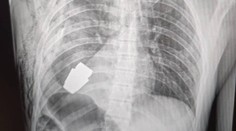

Vojna na Ukrajine Riskantná operácia. Ukrajinskí chirurgovia vyoperovali z hrude vojaka nevybuchnutý granát TASR 12. 1. 2023